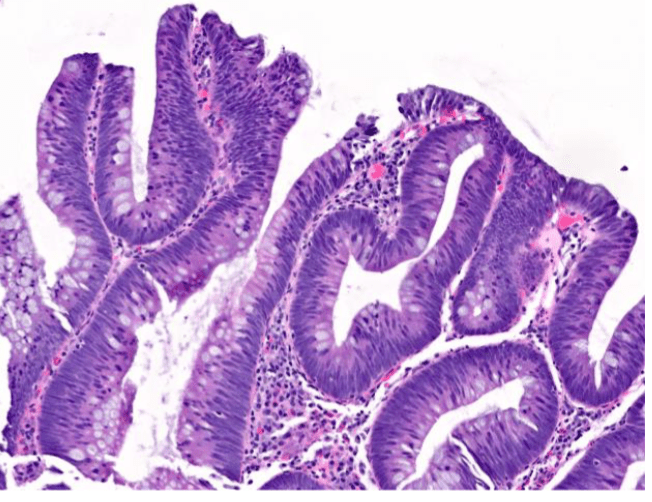

The areas of the body most common to find the above pictured structure

GI, respiratory

Mucosa Associated Lymphatic Tissue

Which image shows malignant colonic mucosa